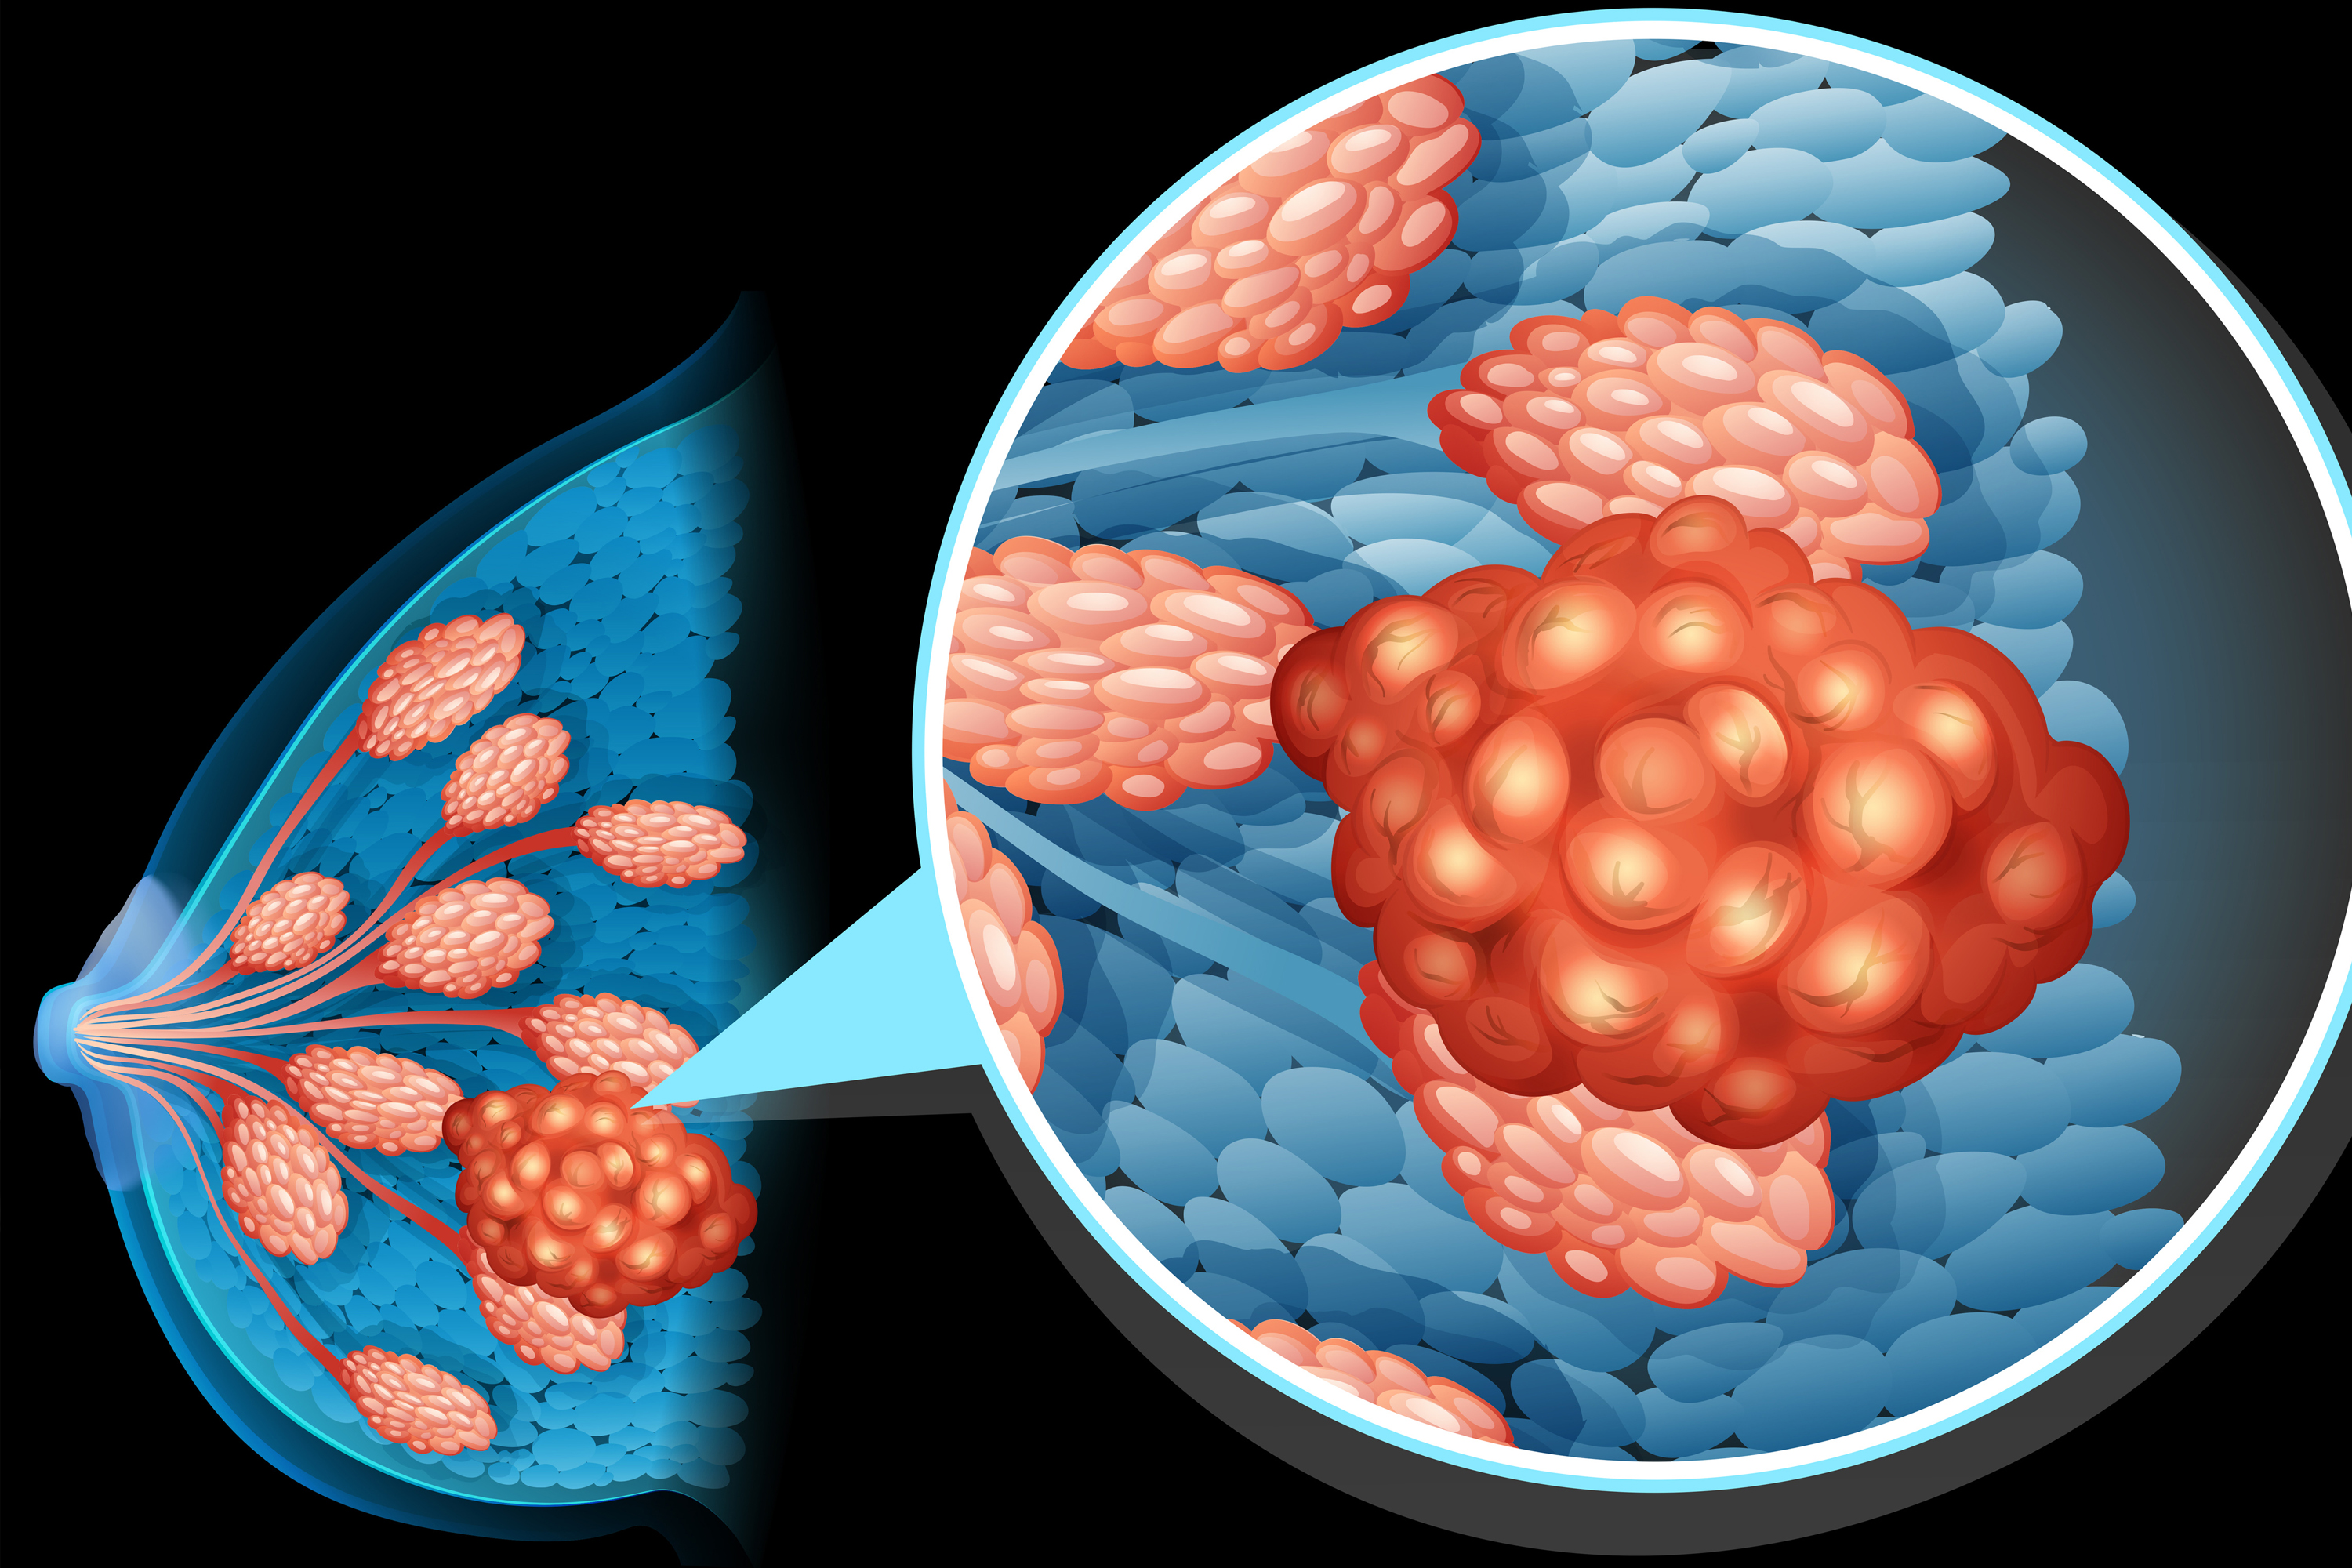

健康・医学 Breast Cancer T-DM1/Brain SRS May Increase Risk of Radionecrosis in Breastの詳細情報

T-DM1/Brain SRS May Increase Risk of Radionecrosis in Breast。Breast Disorders in Arabic 12 ( Breast cancer ,Treatment 1。New Standard of Care in Triple-Negative Breast Cancer?。乳がんに関する最新の情報を提供するモノグラフ。- タイトル: Breast Cancer- 編集者: B. Hoogstraten, I. Burn, H.J. G. Bloom- 出版社: Springer-Verlag- 内容: 乳がんに関する最新の情報を提供するモノグラフ- 特徴: 病理学、診断、治療法についての詳細な章を含む- シリーズ名: UICCご覧いただきありがとうございます。High-grade DCIS Detection Rates Increase in Older Women。病理学や治療法についての詳細な章を含む。介護アロマテラピー入門 : 香りでこころとからだを癒す DVD 介護アロマタッチ。オフィス・トウェンティーワン 薬鑑2015 OFFICE21 持参薬鑑別システム。